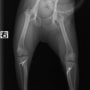

■ 症例24 キャバリア 7か月

左右膝蓋骨内方脱臼(左:グレードⅣ 右:グレードⅢ)

以前から左右後肢の跛行が認められ、整形外科学的検査・レントゲン検査により左右の膝蓋骨脱臼が認められた。症状が重度である左膝の膝蓋骨脱臼整復術を行った。外科手技は縫工筋及び内側広筋の解放、脛骨粗面の外側転位、滑車ブロック形造溝術、内外側関節方の縫縮を実施した。術後一か月時点で、左の膝蓋骨は安定しており経過は良好である。

本症例は成長期における重度の膝蓋骨脱臼であり、術後の再発の可能性もあるため、経過をしっかりと観察していく必要がある。また、今回手術を実施していない右膝に関しても経過を観察し、手術を検討していくこととする。